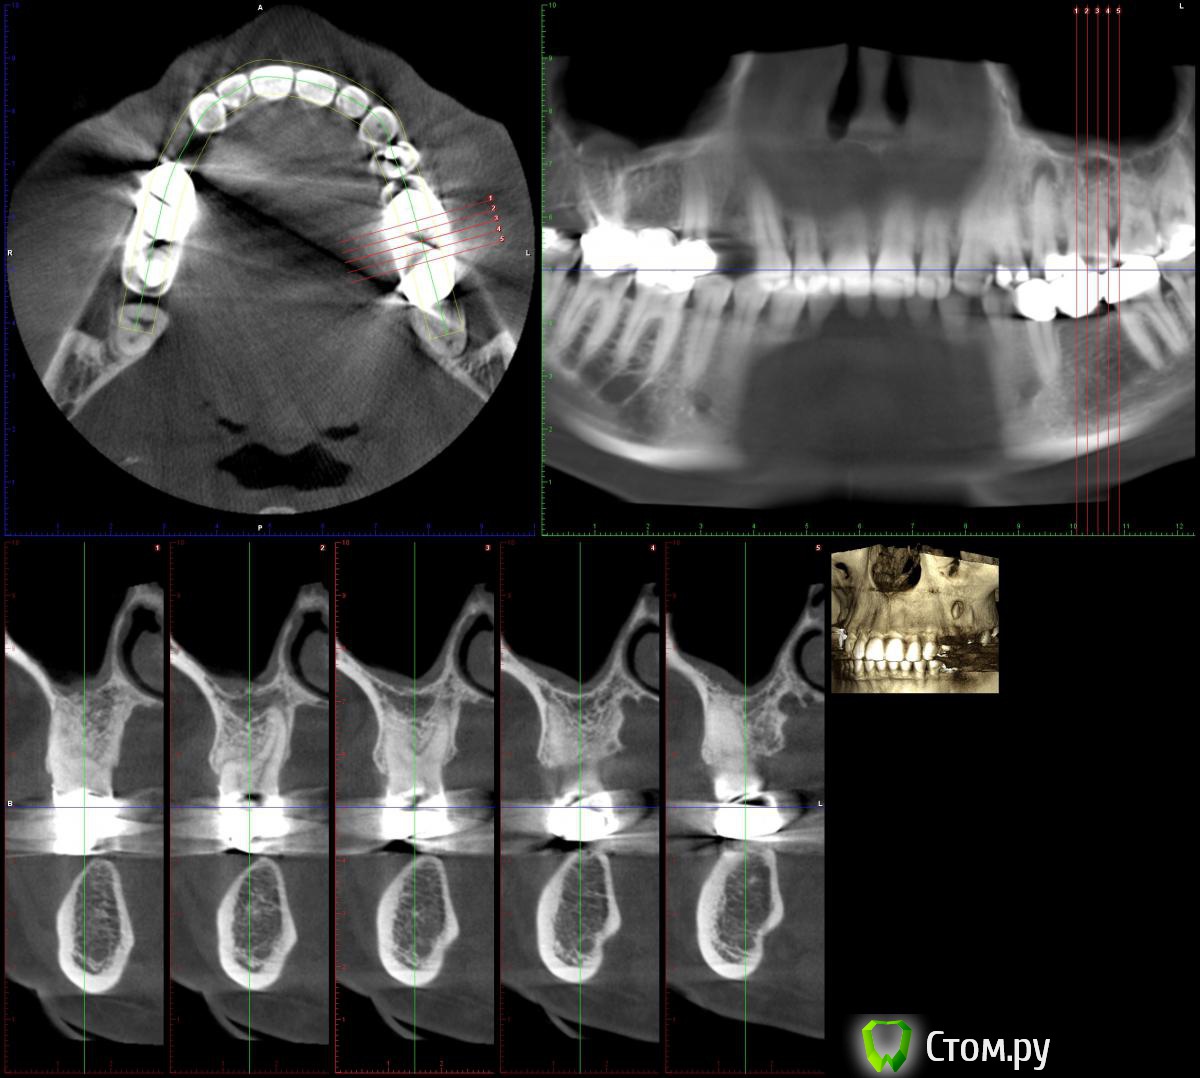

lonely_jack Опубликовано 19 февраля, 2014 Поделиться Опубликовано 19 февраля, 2014 Всем доброго времени суток Принесли КТ для планирования имплантации в области 14 зуба, а там...В области 25 явно напрашивается цистэктомия ( ну и как я думаю удаление 25)... Отсюда пару вопросов:1. Возможность одномоментной имплантации? (естественно с графтом и мембраной)2. Нужно ли на гистологию? (сам думаю, что нет)3. В области 26 и 27 также имеются разрежения (срезы одинаковые, поэтому выкладываю только 26), но с корнями вроде бы не контактируют. Это рисунок кости или все таки стоит насторожиться? Ссылка на комментарий